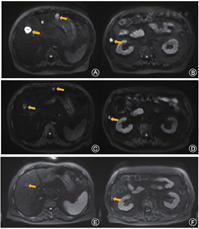

2019年12月PSA水平缓慢上升到18.49 ng/ml,且2019年10月复查骨扫描和PSMA-PET/CT提示患者部分肋骨及右侧髋臼新发病灶,余部分病灶较前范围稍大、血运代谢稍增高。遂开始予多西他赛联合地塞米松(DP)方案化疗。患者完成DP方案9周期化疗,PSA降至1.72 ng/ml。2020年7月患者因盆腔隐痛行盆腔MRI及PSMA-PET/CT检查,发现精囊转移灶,行减症放疗后患者症状缓解,复查盆腔磁共振提示精囊病灶变小。

2020年11月患者PSA升高至3.4 ng/ml,伴随新发后肋部疼痛,需口服镇痛药物缓解。复查PSMA和SSTR标记的PET/CT,均发现新发后肋部转移灶及多发肝脏病灶。患者进一步行CT引导下肝脏病灶穿刺活检,病理诊断:肝组织内见癌细胞浸润。免疫组化染色检查:PSA(-), P504S(-), syn(-), cgA(+), CD56(+), Ki-67(80%+), CK(+),支持小细胞神经内分泌癌转移。穿刺病灶组织及外周血另送基因检测,提示肿瘤细胞TP53和PTEN基因突变,未见胚系基因突变。于2020年11月行多西他赛联合卡铂方案化疗,化疗后第7天患者出现血小板减低(CTCAE 4级)、白细胞减低(CTCAE 3级)、恶心(CTCAE 2级)和乏力(CTCAE 2级)。对症支持治疗1个月后患者症状完全缓解,指标恢复正常。自2020年12月开始予ADT联合恩扎卢胺治疗。监测PSA略有下降,最低降至1.63ng/ml,2021年1月及2021年3月复查肝脏MRI提示转移灶明显缩小或消失。